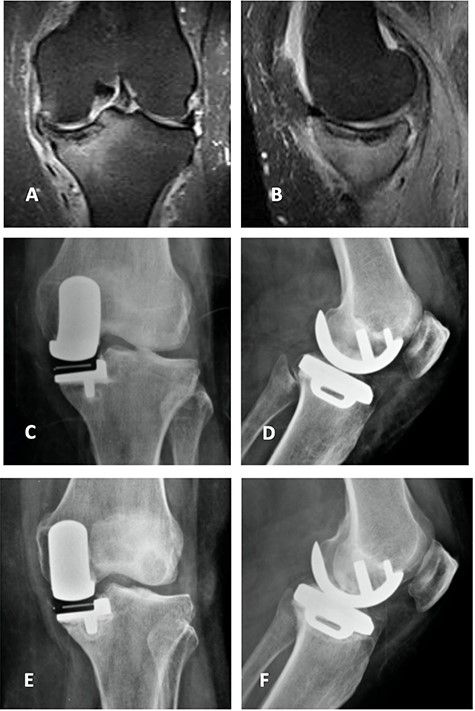

Top: anterior (left) and lateral view (right) X-ray images of the immediate postoperative period (medial UKA); Bottom: anterior (left) and lateral view (right) X-ray images of the same patient with 5 months of follow-up with tibial component loosening.